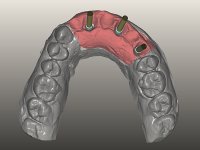

O paciente foi observado conjuntamente e a dúvida que surgiu de imediato foi se seria possível com a regeneração óssea a efectuar poder ser reabilitada naturalmente a zona das papilas interdentárias. Nesse sentido foi feito um enceramento de diagnóstico que contemplaria as duas hipóteses, utilizando ou não a cerâmica gengival. A confecção desse enceramento foi fundamental para expor ao paciente a dificuldade da reabilitação. O wax-up deu origem a um mock-up que foi aprovado pelo paciente e que simultaneamente serviu de guia imagiológica. O caso foi planificado cirurgicamente e realizada uma guia cirúrgica com que foram colocados os implantes. Após 10 semanas foi feita a 1ª impressão para confecção da ponte provisória. Foram criados os primeiros perfis de emergência na gengiva artificial e foi digitalizado o modelo. Por processo de CAD-CAM foi confeccionada uma ponte provisória aparafusada baseada no enceramento de diagnóstico. A ponte trabalhou durante 8 semanas os tecidos moles que foram fielmente copiados numa impressão com técnica de moldeira aberta. Os transferes foram individualizados com resina composta para copiarem fielmente os perfis de emergência criados pela ponte provisória. Confeccionado o modelo de trabalho definitivo, foi realizada uma infra-estrutura em zircónio seguindo a orientação do enceramento de diagnóstico. O assentamento da infra-estrutura foi testado em boca e simultaneamente foi novamente impressionados os tecidos moles com um silicone fluido. Nessa consulta foi feito o levantamento da cor. Os dentes 13 e 23 apresentavam uma saturação anormalmente forte que resolvemos não valorizar, optando por privilegiar a relação com o sector antero-inferior. Foi realizada uma nova gengiva artificial com a impressão que acompanhou a impressão de arrasto com a infra-estrutura. Após a colocação da cerâmica na infra-estrutura foram coladas as meso-estruturas. O trabalho final foi aparafusado lentamente permitindo a adaptação dos tecidos moles.